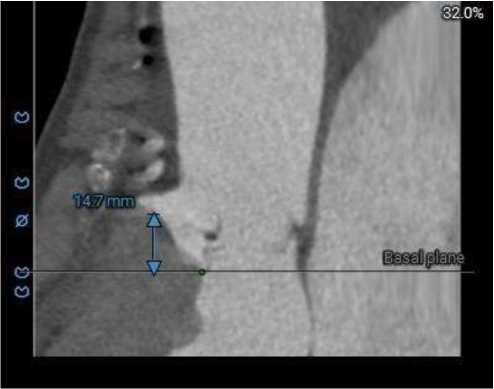

三叶式主动脉瓣,中度钙化,钙化主要分布于瓣叶附着缘及对合缘,钙化分布不均,左冠窦相对较重,右窦和无窦瓣叶对合缘处存在增厚及钙化粘连;

HU850

虚拟瓣环与水平夹角